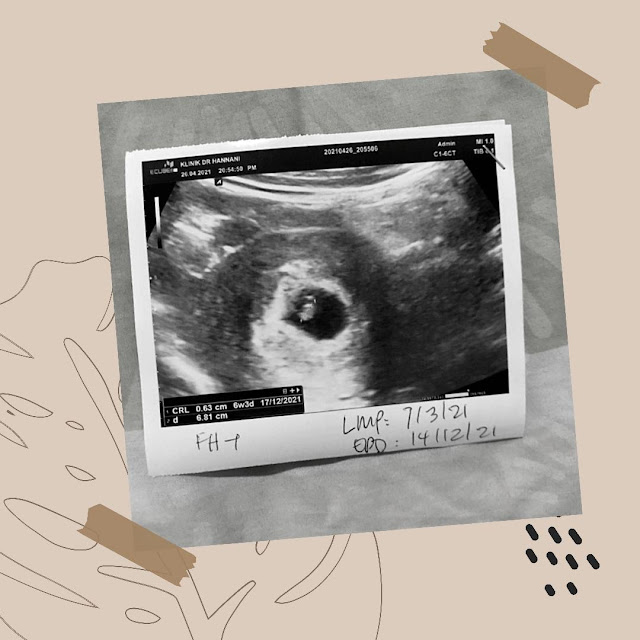

8 Minggu kandungan

Maka, disambung lagi keterujaan aku dengan mengajak Madon ke klinik untuk buat pengesahan kehamilan. Aku taknak berhenti teruja bila baca macam-macam dekat Pakcik Google ni di mana kandungan luar rahim boleh berlaku dalam tempoh awal ni.

keadaan awal buat penghuni pertamaku

Tuu diaaa, alhamdulillah. Tak lekang aku ucapkan alhamdulillah Doktor cakap baby dalam kandungan sihat, HeartBeat dengar jelas. Tak lekang senyuman di bibir.. Tak henti aku beritahu ibu, bapa, mak dan adik beradik aku. Walaupun tahu ianya masih awal. Tapi aku tak dapat kawal perasaan keterujaan aku tu. hehehe. Tapi takde lah over bagitahu dekat sosial media sana sini. Setakat sahabat dan sepupu yang terpaling rapat dan siap bagi amaran dekat ibu jangan war-war kan sampai betul-betul kuat kandungan aku. EDD aku kalau tepat tarikhnya sama betul dengan adik aku yang bongsu. Syakila. Hahaha. Adakah tarikh tersebut atau 12.12 ? tak sabar !